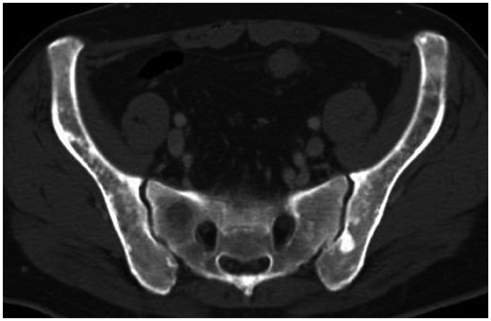

Figure